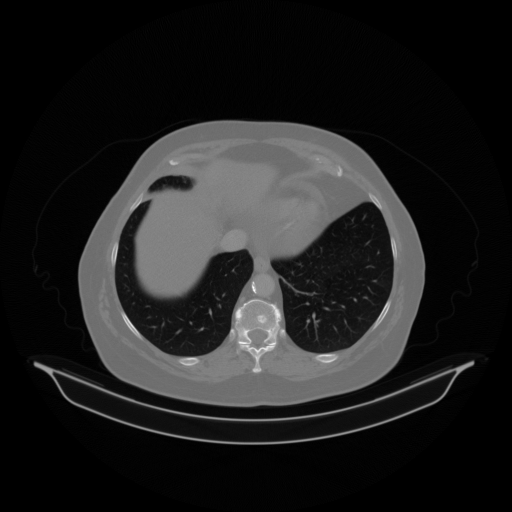

Original VENOUS CT scan

Full window (WL 1023.5, WW 4095 β†’ Low βˆ’1024, High +3071)

Lung window (WL -600, WW 1500 β†’ Low βˆ’1350, High +150)